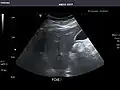

Abdominal Ultrasound (Full Exam)

STRUCTURED REPORT

(Technique: Transabdominal ultrasonography; Device: Toshiba Aplio XG)

Liver: Diffusely homogeneous and normal in echogenicity. No focal mass or contour nodularity. No intrahepatic biliary ductal dilatation.

Portal Vein: Patent main portal vein.

Gallbladder: No stones, wall thickening, or pericholecystic fluid.

Common Bile Duct: Nondilated measuring 1.3 mm at the level of the porta hepatis.

Pancreas: Visualized portions unremarkable.

Spleen: Normal in size.

Kidneys: Right and left kidneys measure 11.5 cm and 12 cm in length respectively. No hydronephrosis. Small left lower pole kidney cyst.

Ascites: None.

Aorta: Visualized portions normal in caliber, 16 x 15 mm.

IVC: Normal.

IMPRESSION:

Normal abdominal ultrasound.